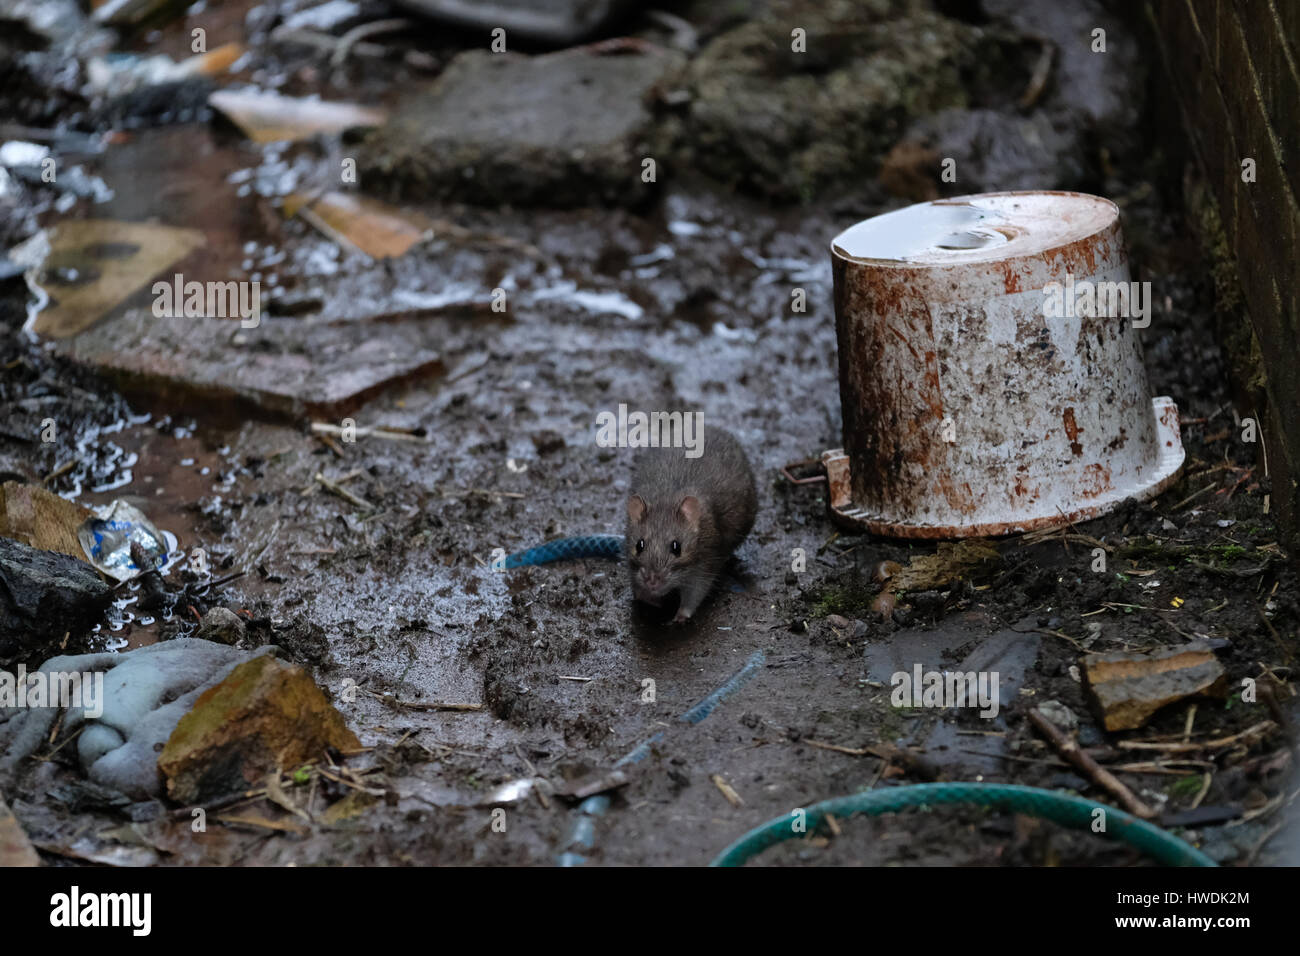

RMK1F9R5–Souris sylvestre, Peromyscus maniculatus, porteur de l'agent virus Sin nombre, de syndrome pulmonaire à hantavirus (SPH) Image Courtesy CDC, 1974.